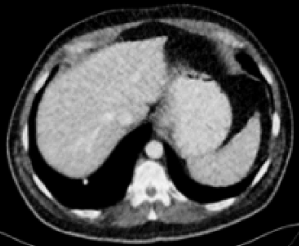

RED-CNN (0.8790)

| RED-CNN+SSWL (0.8901) | RVAE (0.8851) | RVAE+SSWL (0.9023) |

Figs. 3 and 4 demonstrate precise removal of noise from whole scans as well as specific regions of interest (ROIs), proving the effectiveness of our model over baseline architectures and other self-supervised tasks. As shown, both the RVAE and SSWL are able to quantitatively and qualitatively outperform their respective counterparts.